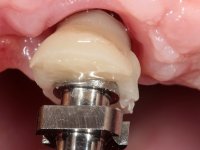

O paciente foi observado conjuntamente e a dúvida que surgiu de imediato foi se seria possível com a regeneração óssea a efectuar poder ser reabilitada naturalmente a zona das papilas interdentárias. Nesse sentido foi feito um enceramento de diagnóstico que contemplaria as duas hipóteses, utilizando ou não a cerâmica gengival. A confecção desse enceramento foi fundamental para expor ao paciente a dificuldade da reabilitação. O wax-up deu origem a um mock-up que foi aprovado pelo paciente e que simultaneamente serviu de guia imagiológica. O caso foi planificado cirurgicamente e realizada uma guia cirúrgica com que foram colocados os implantes. Após 10 semanas foi feita a 1ª impressão para confecção da ponte provisória. Foram criados os primeiros perfis de emergência na gengiva artificial e foi digitalizado o modelo. Por processo de CAD-CAM foi confeccionada uma ponte provisória aparafusada baseada no enceramento de diagnóstico. A ponte trabalhou durante 8 semanas os tecidos moles que foram fielmente copiados numa impressão com técnica de moldeira aberta. Os transferes foram individualizados com resina composta para copiarem fielmente os perfis de emergência criados pela ponte provisória. Confeccionado o modelo de trabalho definitivo, foi realizada uma infra-estrutura em zircónio seguindo a orientação do enceramento de diagnóstico. O assentamento da infra-estrutura foi testado em boca e simultaneamente foi novamente impressionados os tecidos moles com um silicone fluido. Nessa consulta foi feito o levantamento da cor. Os dentes 13 e 23 apresentavam uma saturação anormalmente forte que resolvemos não valorizar, optando por privilegiar a relação com o sector antero-inferior. Foi realizada uma nova gengiva artificial com a impressão que acompanhou a impressão de arrasto com a infra-estrutura. Após a colocação da cerâmica na infra-estrutura foram coladas as meso-estruturas. O trabalho final foi aparafusado lentamente permitindo a adaptação dos tecidos moles.